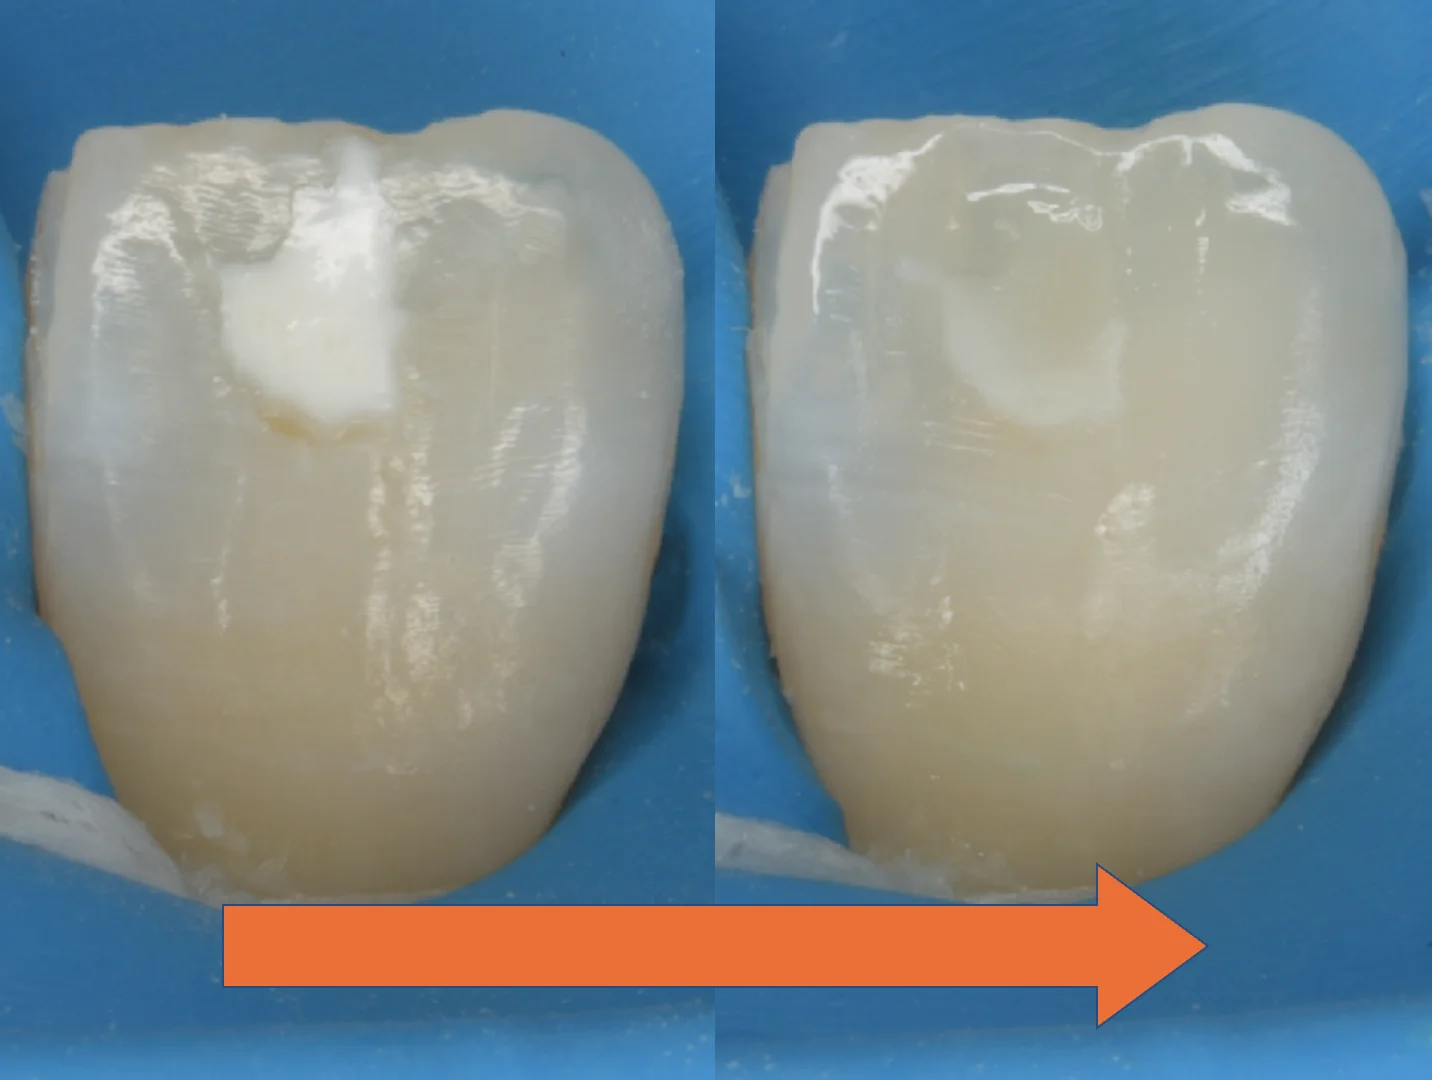

こちらがICONにて処置を行った直後の写真になります。

大分薄くはなっていますが、それでもうっすらと残存しているのがわかると思います。

こう言った場合どう対応するかというと・・・

私の場合はここからホワイトスポットの残存しているところだけを削ってダイレクトボンディングを行います。

ただし、薄く小さくすることができればダイレクトボンディングの際に削る量も最小量に抑えることができる分、ICON治療を挟むメリットは非常に大きいです。